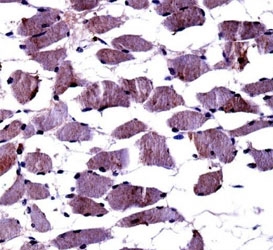

TRKA (also known as NTRK1) is a member of the neurotrophic tyrosine kinase receptor (NTKR) family. This kinase is a membrane-bound receptor that, upon neurotrophin binding, phosphorylates itself and members of the MAPK pathway. The presence of this kinase leads to cell differentiation and may play a role in specifying sensory neuron subtypes. Mutations in the TRKA gene have been associated with congenital insensitivity to pain, anhidrosis, self-mutilating behavior, mental retardation and cancer.

Titration of the TrkA antibody may be required due to differences in protocols and secondary/substrate sensitivity.

A portion of amino acids 769-796 from the human protein was used as the immunogen for this TrkA antibody.